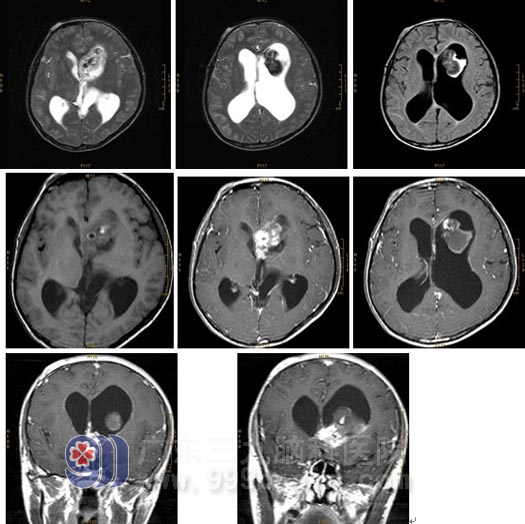

颅脑MRI检查所见:

左侧脑室内示一不规则占位性病变,向下延伸累及视交叉,范围约为4.3×4.2×2.5cm。病变前下部分T1WI呈稍低信号,T2WI及FLAIR序列呈高信号,其内信号不均,可见多发斑片状短T1长或短T2异常信号影,FLAIR序列呈高信号,另尚可见一小圆形各序列内低外环形高信号影;病变后上部分T1WI呈内稍低外环形高信号,T2WI及FLAIR序列呈内不均匀极低外环形高信号;增强后,病变前下部分呈不均匀明显强化,后上部分未见明显强化。幕上脑室扩张,以左侧侧脑室尤著,透明隔轻度右移。MR诊断考虑为左侧脑室内肿瘤合并出血。

病理诊断:海绵状血管瘤(左侧脑室内)。http://www.999brain.com/